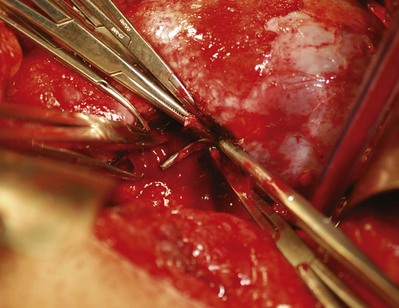

The right renal vein, which is relatively short and does not typically receive large tributaries, is mobilized. The gonadal vein enters the IVC and is ligated before the dissection of the right renal vein to avoid troublesome bleeding. The right renal artery lies posterior to the renal vein along its superior margin and normally runs a retrocaval course (see Fig. 54–37). The renal artery can be isolated to the right of the vena cava. Alternatively, in cases of a large medial tumor or significant nodal disease in the hilum, the renal artery can be controlled between the vena cava and aorta (Fig. 54–88).

The left renal vein passes anterior to the aorta and is longer than the right renal vein. Unlike the right side it receives gonadal, adrenal, and lumbar tributaries, which are ligated and divided. Identifying the left renal artery from the posterior approach is recommended to avoid inadvertent ligation of the superior mesenteric artery, which is on the anterior surface of the aorta 1 to 2 cm cephalad to the left renal vein. Alternatively, the artery can be isolated from an anterior approach by retracting the mobilized vein. The artery is mobilized toward the aorta, ligated, and divided. Two large Hem-o-Lok clips and a 0 silk suture ligature are used to secure the main renal artery with a silk tie on the specimen side, followed by the vein (see Fig. 54–89 [on the Expert Consult website

] and Figs. 54-90 and 54-91). Preoperative arterial embolization permits venous ligation to be performed first, which is occasionally necessary in complex dissections.

Figure 54–89 A, Self-retraining ring retractor is inserted to maintain exposure. B, Left renal vein is mobilized by ligation of its major branches to expose the artery posteriorly.

(Reproduced with permission from Novick AC, Streem SB, Pontes E, editors. Stewart’s operative urology. 2nd ed. Baltimore: Williams & Wilkins; 1989.)